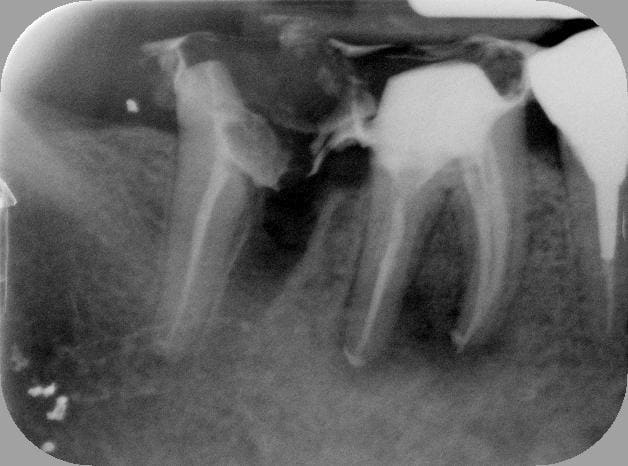

-suite à l'endo+rcr de la semaine dernière sur 46, ce matin: prep, pro 46 47 et amputation de la racine mésiale de 47 en 45min. Sur la radio, il reste encore un peu (;-)) de temp bond.

Retour dans 3 mois pour la suite des opérations.

Pano shpohv - Eugenol

46 47 yiqmod - Eugenol